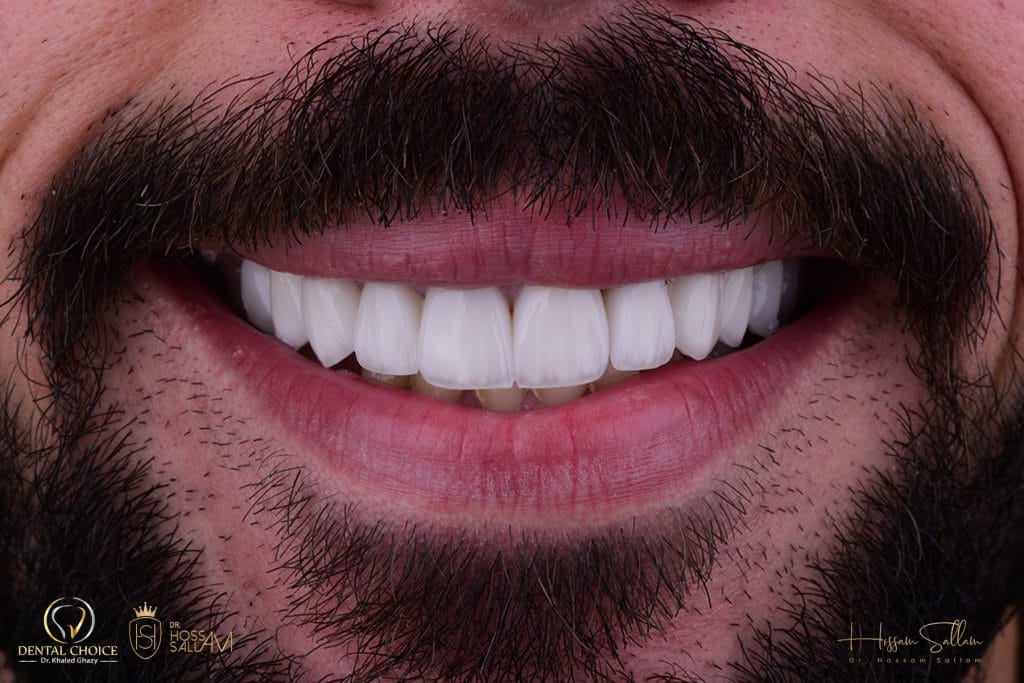

It is an amazing result to see healing in one week

- stippled gingiva

- healthy gingival profile

New bright Smile

frontal view

The difference became clear now

after 2 weeks recall